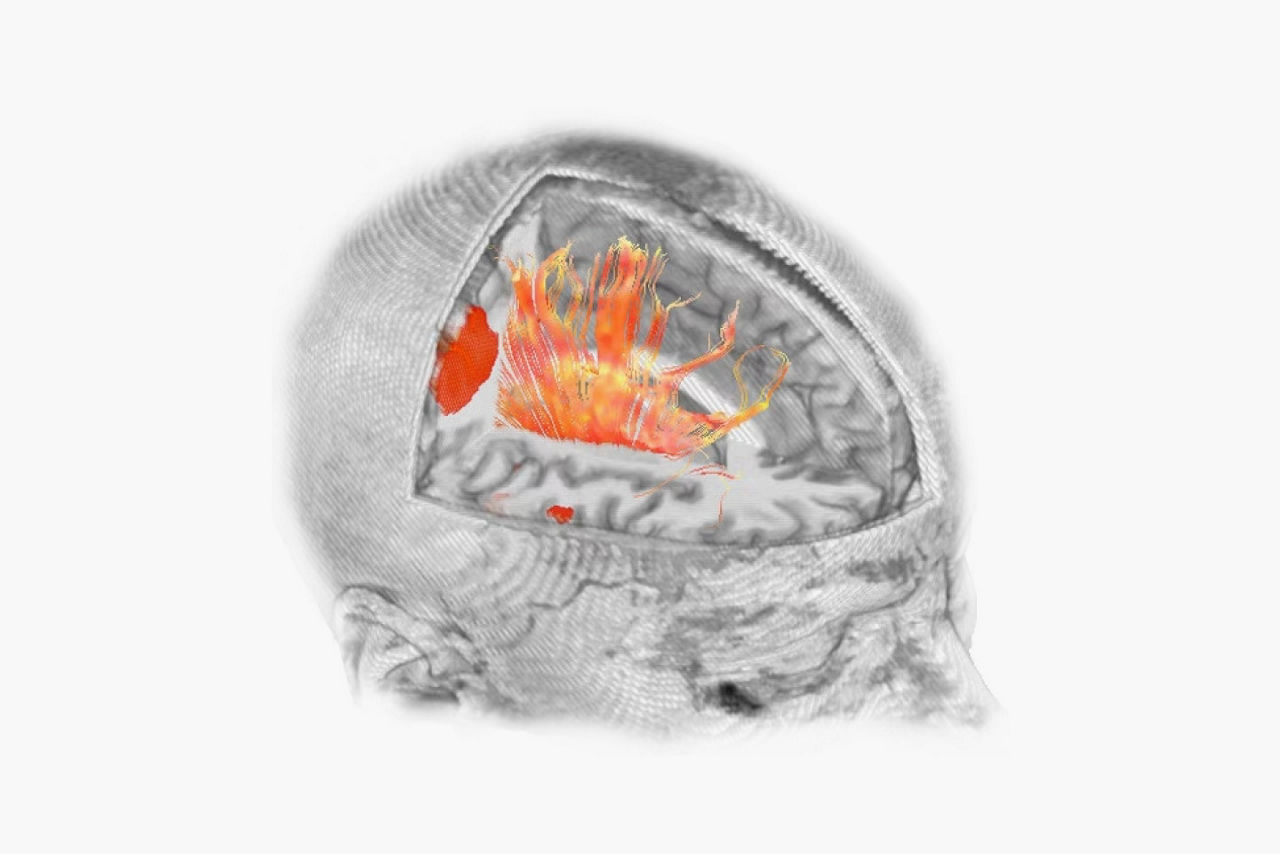

- Sophisticated visualization techniques that fuse analysis results with anatomical data

- Clear visualization with color activation maps and interactive thresholding

- Ability to transfer activations into high resolution 3D DICOM data sets for neurological applications